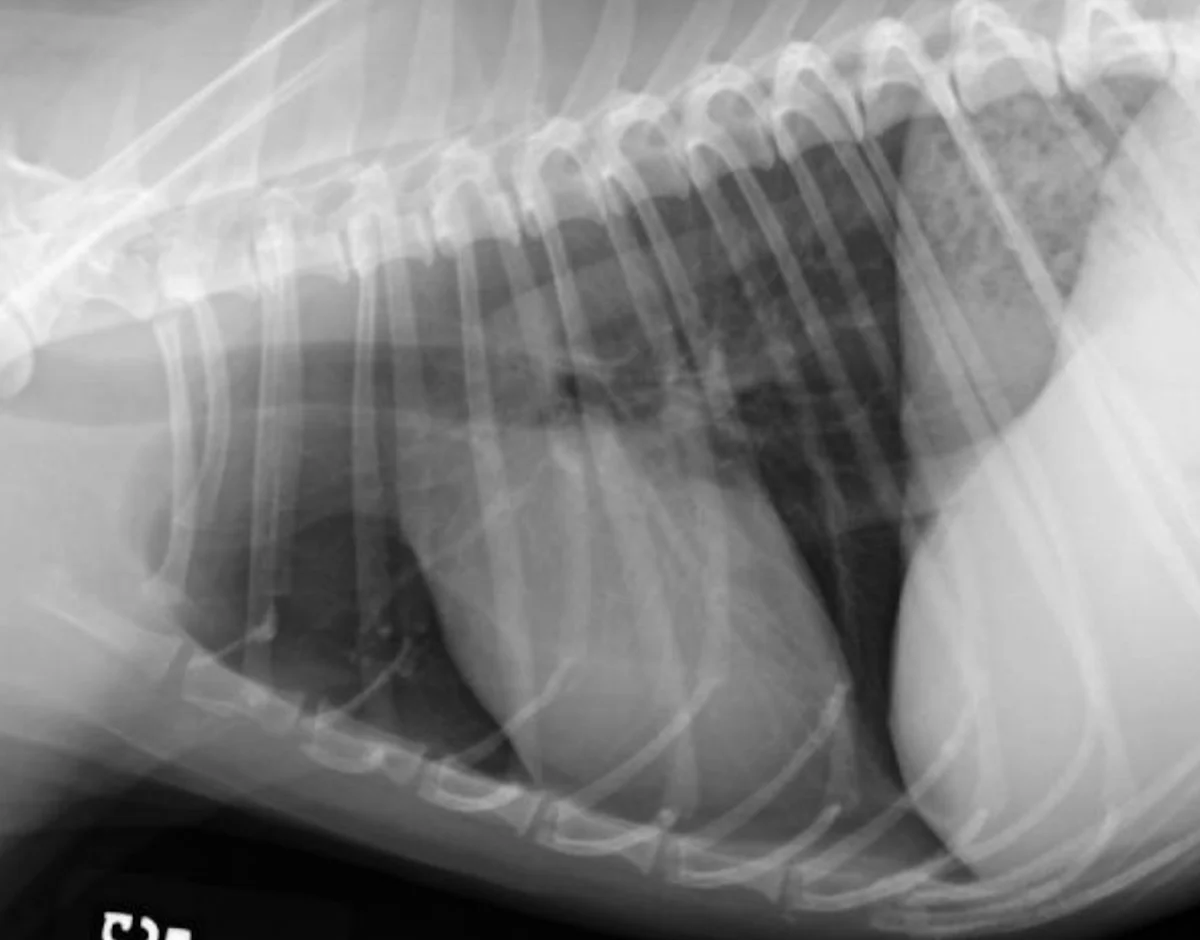

Thoracic radiographs should always be evaluated in the exact same position and correct orientation (ie, left lateral, ventrodorsal or dorsoventral, and right lateral) (Figure 2).

Right lateral (A), left lateral (B), and ventrodorsal (C) thoracic radiographs from a 7-year-old mixed breed neutered male dog. Right lateral (D) and ventrodorsal (E) images from a 4-year-old neutered male domestic shorthair cat. In both cases, the radiographs were deemed normal.